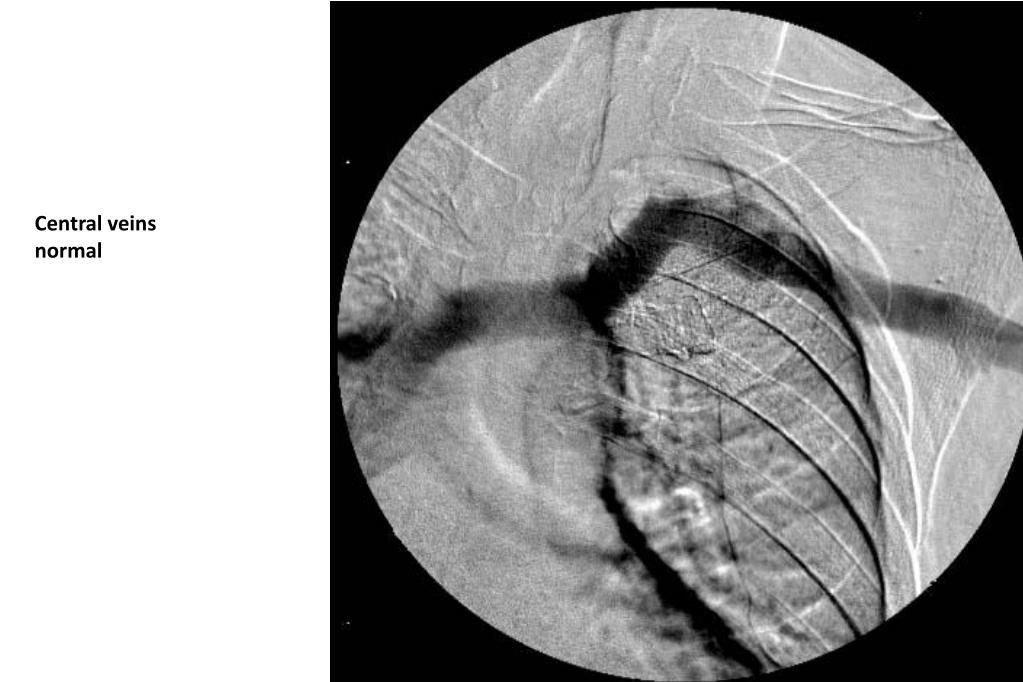

37. Central veins normal

38. SVC normal